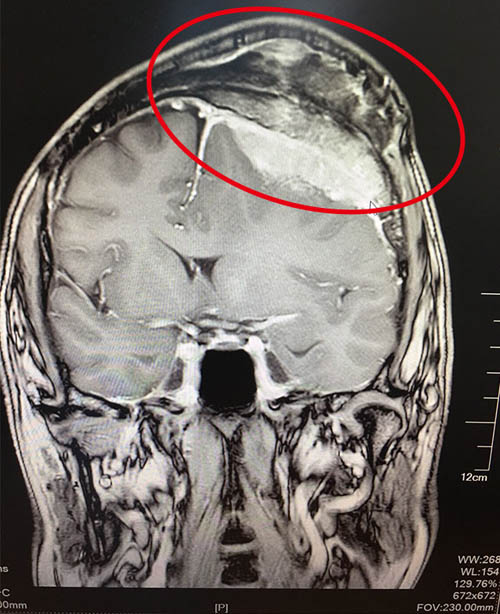

好景不長,兩年前的夏天,王先生突然莫名的頭暈,他以為是天氣熱,干活勞累所致,就沒當回事。沒想到在今年7月份,頭暈加重,發(fā)作頻繁,不能忍受。家人隨即勸說王先生,將他送到當?shù)蒯t(yī)院,做CT檢查顯示:顱內占位性病變,醫(yī)生說情況有些嚴重,需要轉院。懷著憂心忡忡的心情,王先生在上海某三甲醫(yī)院做了核磁共振檢查,結果讓人震驚:左額凸面占位伴顱骨及皮下侵犯,考慮間變血管外皮瘤,也有可能是淋巴瘤。醫(yī)生說由于腫瘤巨大,性質難以確定,術后可能出現(xiàn)偏癱、失語等并發(fā)癥,手術難度高,風險大,建議他們轉到其他醫(yī)院進行治療。聽醫(yī)生這么說,王先生和家人才感到危機四伏。

術前核磁顯示:左側額部(大腦凸面)侵襲性腦瘤,侵及顱骨和軟組織